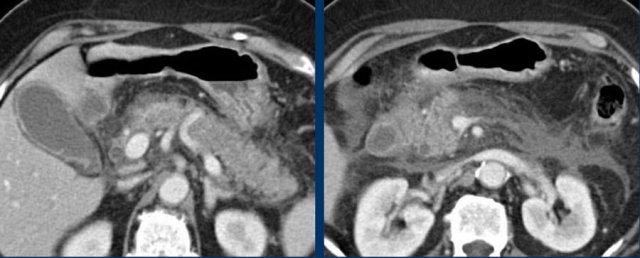

Đây là hình ảnh của một bệnh nhân viêm túi mật cấp giai đoạn sớm.

Lưu ý sỏi gây tắc nghẽn (mũi tên), thành túi mật dày và túi mật phình ra phía thành bụng khi ấn, cho thấy áp lực trong lòng túi mật cao.

CRP là 110, xác nhận chẩn đoán viêm túi mật cấp.

Viêm túi mật giai đoạn tiến triển với mỡ viêm (dấu hoa thị) xung quanh đáy túi mật.

Đây là hình ảnh mạc nối lớn di chuyển đến vị trí túi mật để bao bọc ngăn ngừa thủng có thể xảy ra.